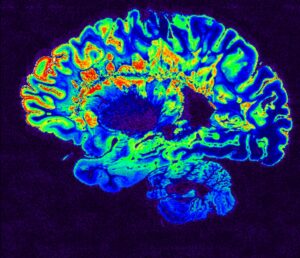

The heart of Brainomix’s advancements is e-Stroke – a software developed by Oxford University academics and physicians which detects through AI the affected area by a stroke.

E-Stroke reduces the diagnosis of a stroke from 20-40 minutes minimum, if done manually, to just a few minutes due to its ability to generate critical information from simple brain scans using advanced imaging.